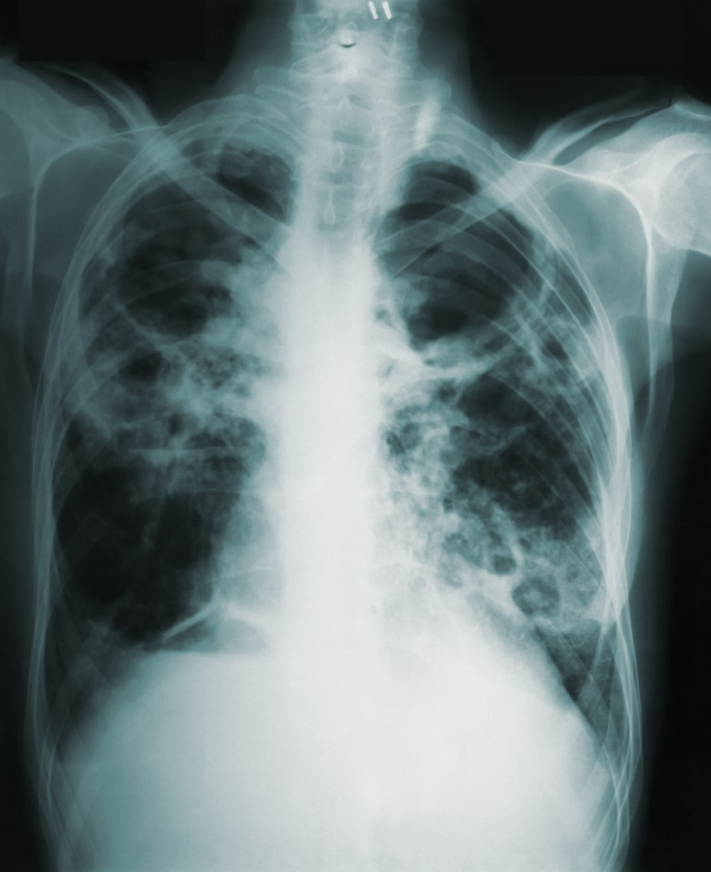

Tuberculosis (TB) remains a leading cause of death among people living with HIV (PLHIV) in the Philippines, with one in five HIV-related deaths attributed to TB, the Department of Health (DOH) said on Sunday, Aug. 24. Health experts emphasized that PLHIV are more susceptible to contracting TB due...

In a bid to tackle the alarming rates of tuberculosis (TB) in the Philippines, Department of Health (DOH) Secretary Teodoro Herbosa has announced efforts to align with global initiatives to end tuberculosis by 2030. Photo from UP PGH Pulmonary Medicine X account Highlighting the endemic nature of...

Department of Health (DOH) Secretary Teodoro Herbosa revealed on Wednesday, Feb. 14, that the Philippines is the fourth country in the world with the highest tuberculosis (TB) incidence. (Unsplash) "Ibig sabihin nito, ang bansa pala natin ay nagpo-produce ng TB at ikinakalat sa mundo, 4th tayo sa...